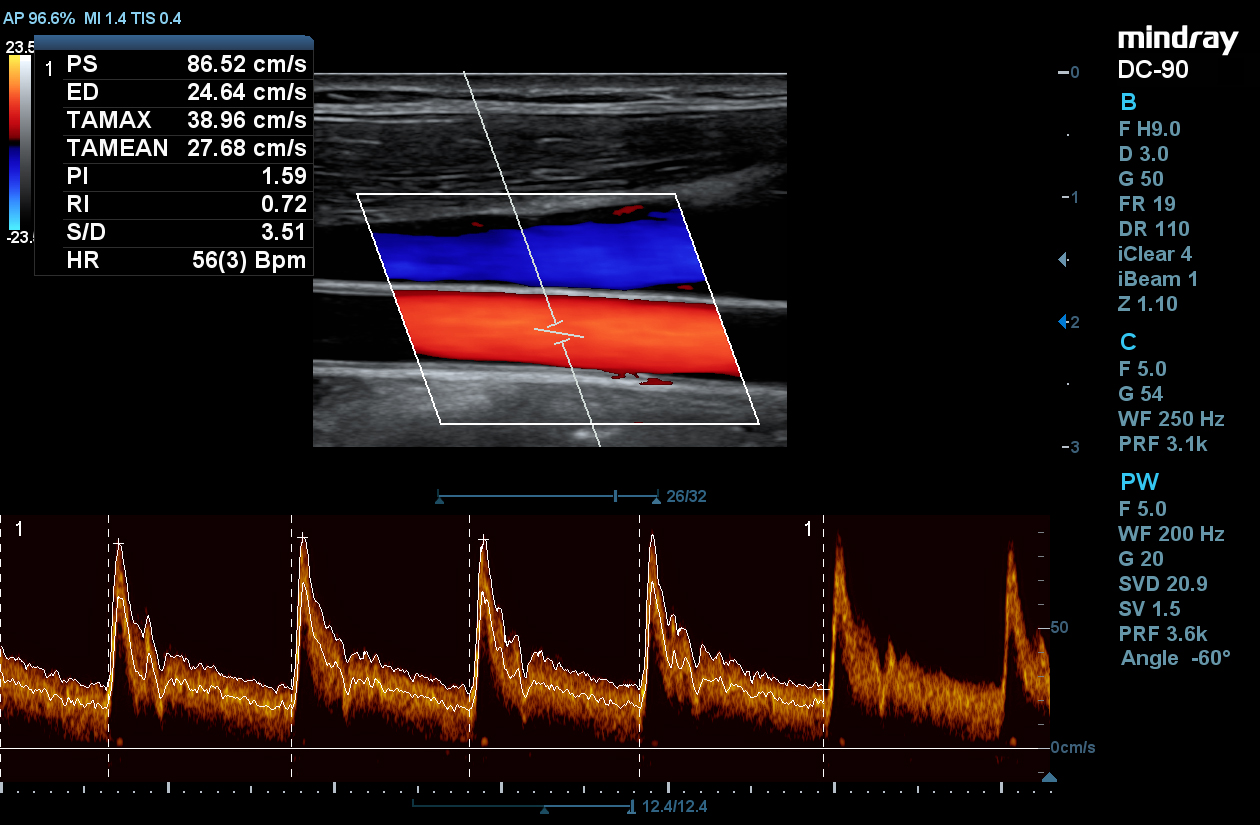

STE

Mindray’s Sound Touch Elastography (STE) utilizes exclusive Ultra-Wide Beam Tracking technology to provide comprehensive quantification metrics and dynamic visual display of tissue stiffness for enhanced diagnostic confidence. Using real-time and rapid data acquisition from a wide beam single pulse, STE is designed to reduce noise caused by motion artifact for improved efficiency and accuracy of measurements.